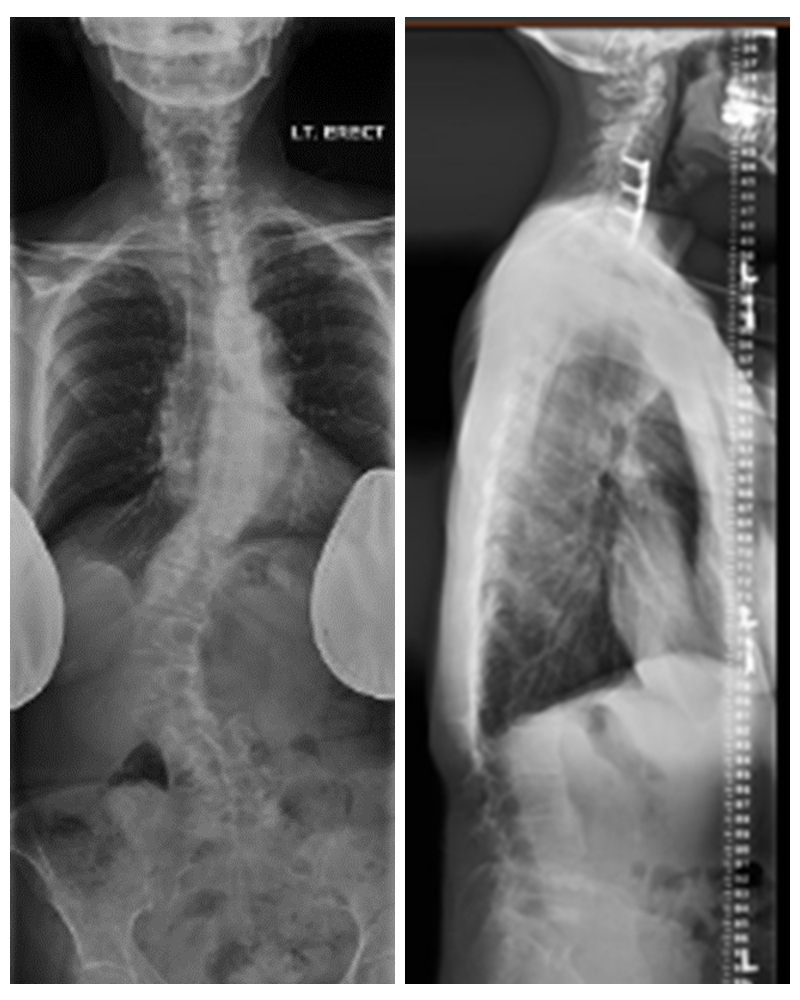

术前X线

术前MRI示L4/5左侧神经根管狭窄